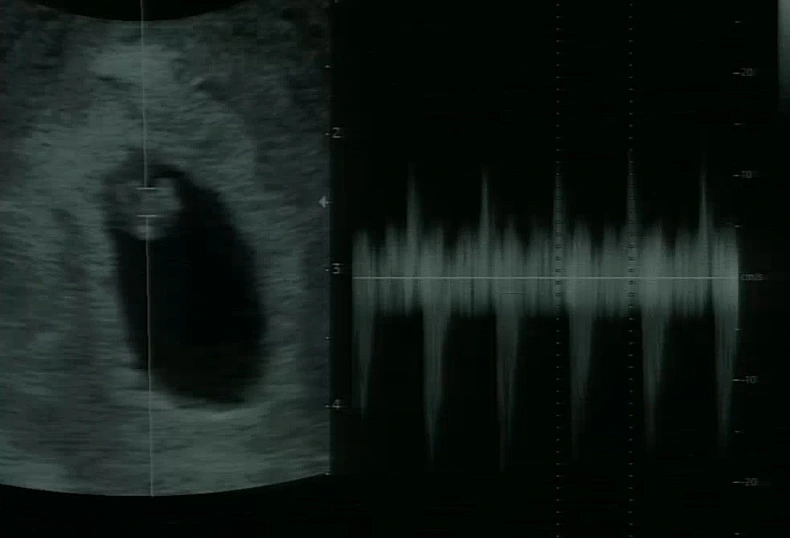

2022년 2월, 내 나이 서른넷에 남편과 손잡고 난임병원을 방문했다. 2018년 8월, 서른 살에 결혼 후 신혼기간을 충분히 즐기고 아기를 갖기 원했기에 크게 걱정하지 않았지만 시간이 흐르면서 생각이 바뀌기 시작했다.

다소 긴장했지만 검사를 마쳤고 부부 모두 큰 이상은 없다는 결과를 들었다. 특히 내 난소나이가 29세라는 사실에 의기양양해졌다.

그렇게 시간이 흘렀다. 동네 정형외과에서 꾸준히 치료받았지만 근본적으로 해결이 되지 않고 만성통증으로 진행되었다. 결국 지인이 소개해준 한의원까지 방문하게 되었고 호전되기 시작했으나 치료 1회 만에 임신사실을 알았다.